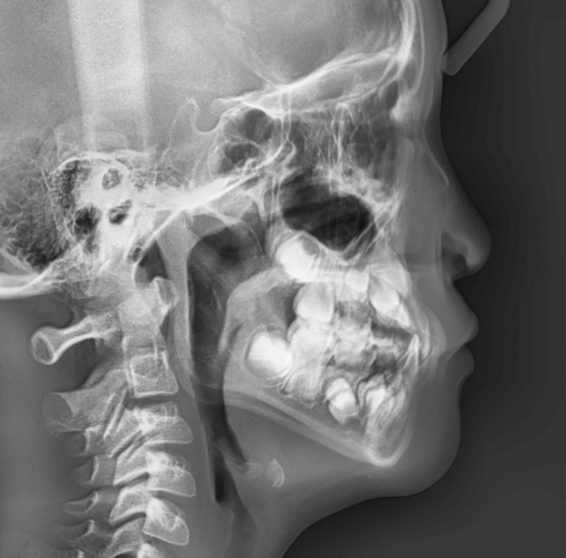

| 年齢・性別 | 8歳3ヶ月の男児 |

|---|---|

| 主訴 | 上顎前歯の位置異常に不安を抱え、歯並びと将来的な咬合状態を整える目的で来院された患者様です。 特に左側の前歯(中切歯および側切歯)の萌出が確認できないことがきっかけとなりました。 |

| 治療期間・回数 | 約5年10ヶ月 |

| 費用 | 460,000円(税別) |